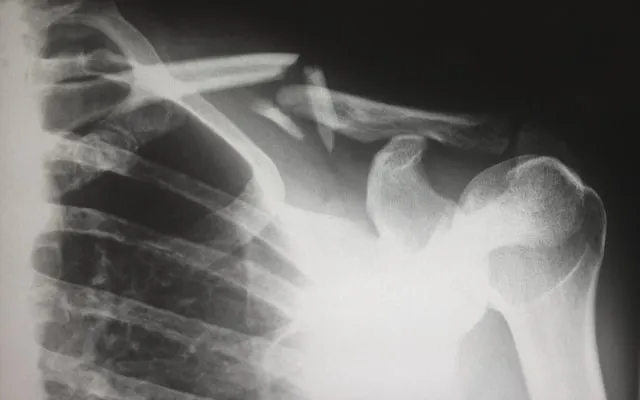

Meki kalus postupno se mineralizira i pretvara u tvrdi koštani kalus. Osteoblasti talože kalcij i fosfor, gradeći novu koštanu strukturu. U ovoj fazi rendgenska slika počinje pokazivati vidljive znakove zarastanja. Pacijenti često osjećaju značajno smanjenje boli, no to ne znači da je kost potpuno zarasla – prerano opterećenje može poremetiti ovaj osjetljivi proces.